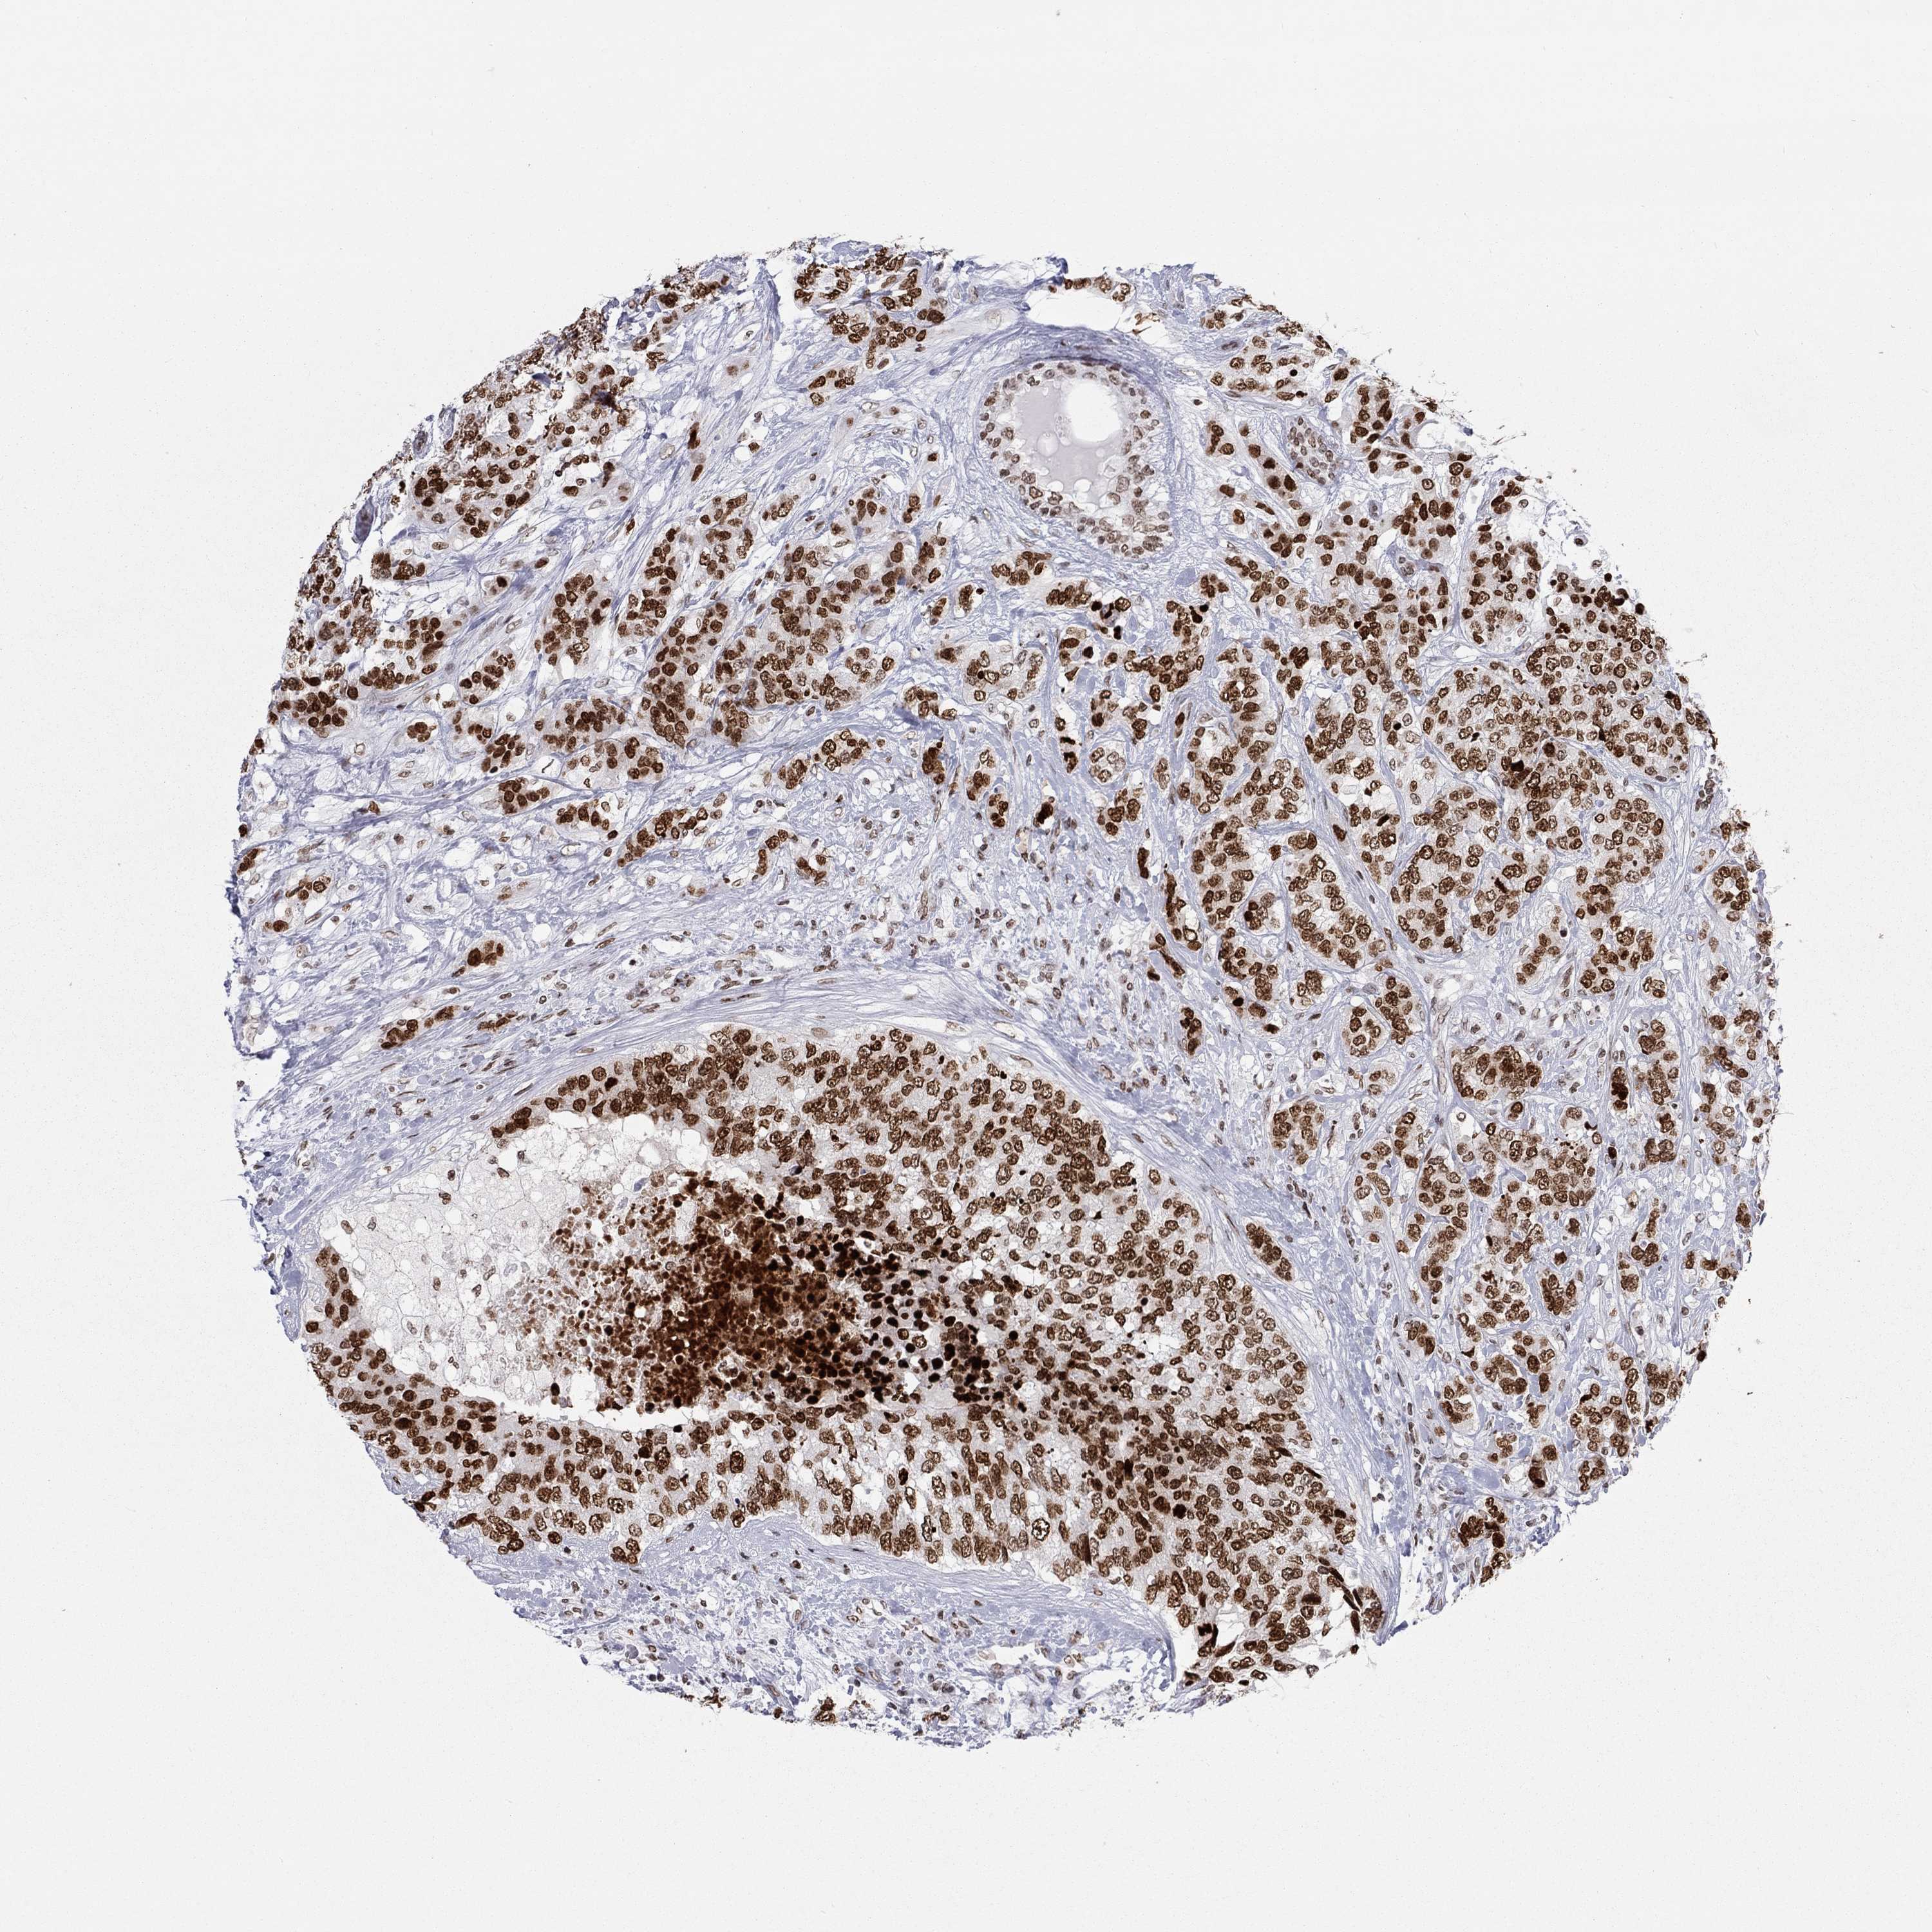

H2AX

• H2AX